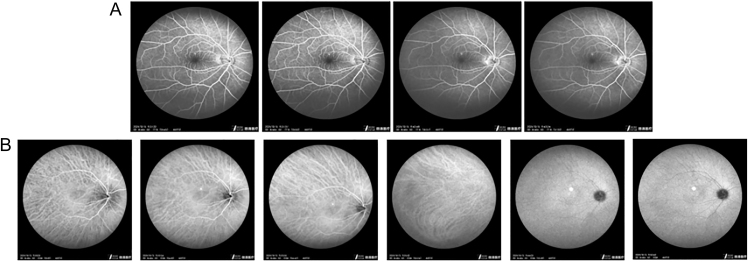

Summary: Dysthyroid optic neuropathy (DON) is the most serious complication associated with Graves' orbitopathy (GO). The primary treatment approach for DON is high-dose intravenous methylprednisolone infusion and decompression surgery. However, not all patients are suitable candidates for or can tolerate these two treatment options. Here, we present a patient diagnosed with DON in the left eye and central serous chorioretinopathy (CSC) in the right eye. Considering that glucocorticoids are contraindicated for CSC and that the patient refused orbital surgery, we opted for intravenous tocilizumab (6 doses of 8 mg/kg every 4 weeks), a monoclonal antibody against the interleukin-6 receptor. After tocilizumab infusion, the disease severity in the left eye improved from DON to moderate to severe GO, with magnetic resonance imaging showing a considerable reduction in inflammation in all affected muscles. Moreover, no adverse effects were observed in this patient. Similarly, two case reports and an observational study including nine patients with DON showed good clinical results after tocilizumab infusion, with no adverse effects having been observed. Our patient was primarily treated with tocilizumab just like one of the previous cases who had uncontrolled diabetes. Tocilizumab could potentially be considered one of the treatment options for DON patients, especially those in whom glucocorticoid therapy is inappropriate. Nonetheless, high-quality studies are warranted to verify the indications for this treatment.